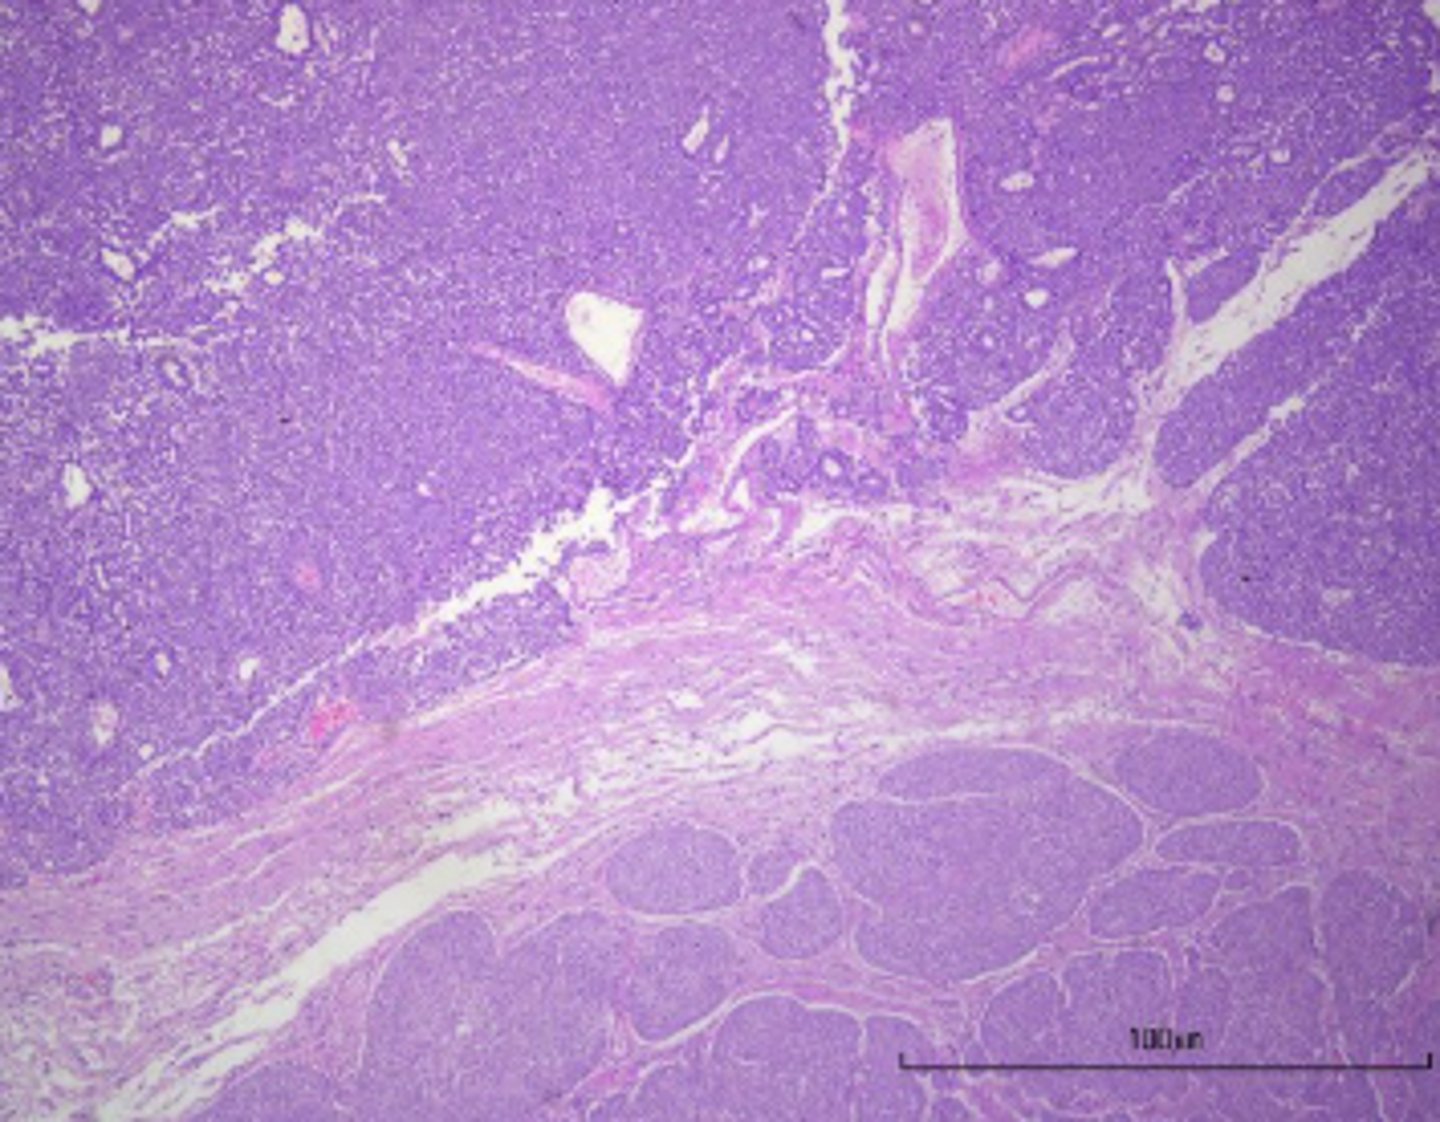

Cholangiohepatitis

-inflammation of the biliary ducts and parenchyma

-expanded bile ducts

What has caused this histologic appearance of this liver?